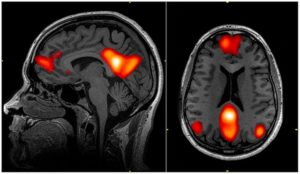

脳というのは様々な部分がつながって様々なネットワークを作っているのですが、その中でも強大なネットワークの一つにデフォルトモード・ネットワークというものがあります。

引用元:wikipedia「デフォルトモード・ネットワーク」

このデフォルトモード・ネットワークは何もしていない時の心の状態や想像、体の内部状態(お腹が痛い、のどが渇いた)といった情報処理に関わっているものなります。

ごくごく簡単に行ってしまえばぼんやりしている時の脳活動というのはデフォルトモード・ネットワークが活発に働いている状態ということになります。